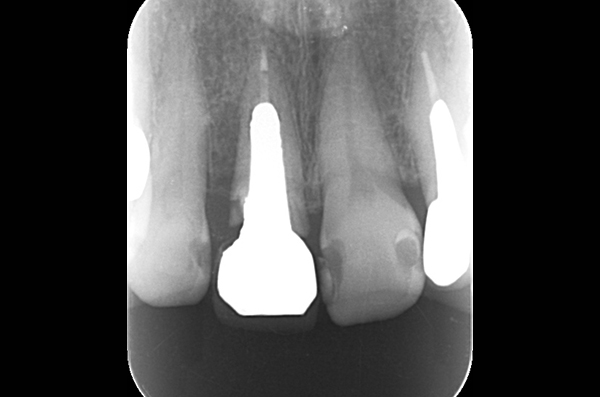

右上1抜歯即時埋入

40代女性。部位右上1に対して抜歯即時インプラント治療を行った。治療期間4ヶ月。

費用 39万円(税別)

- 喫煙者の方は、インプラント周囲炎やインプラント脱離のリスクが高まります。

- 当院ではナイトガードを使用していただいています。

- 骨幅が足りない、神経までの距離が短いケースは手術を行えないこともあります。